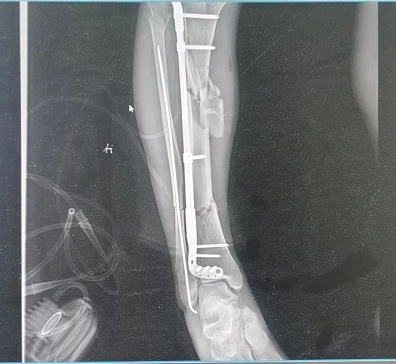

医生为患者复位骨折部位。通讯员陈梦圆 周丽 摄

接诊的骨科医生贾炬川为周先生检查,发现患者右腿胫骨、腓骨多处骨折,小腿骨头断为7截,伤情严重,如果恢复不佳,可能会导致小腿短缩、旋转、畸形等情况。经过初步清创、止血等处理后,周先生被收治入院等待手术。由于患者是开放性骨折,断骨戳破皮肤,可能造成感染,还要先控制感染后,才能为其进行手术。术中,肖飞医生小心翼翼地为患者复位骨折部位,并用钢板钢钉固定。目前,周先生术后恢复良好,出院后经过一段时间的康复训练,不会影响正常生活。(长江日报记者武叶 通讯员陈梦圆 周丽)